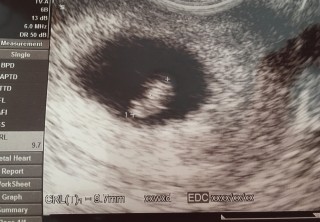

二人目の妊娠です。6週4日、排卵検査薬と卵胞チェックをしていたので週数の狂いはありません。 5.7ミリの胎芽と心拍も確認できました。 稽留流産の経験があったので不安でしたが 「これだけ育ってれば大丈夫だよ!」と膝をたたいてもらえました☆ 元気に育ってくださいね(*^^*)

先週ツワリが酷くて飲み食い出来ず病院に行った時は、流産しかけていると怒られました。 妊娠悪阻で点滴&薬でなんとか過ごしました。 前回、繋留流産した為かなり不安でしたが無事に心拍確認できて順調ですと言われ安心しました。 それから休職して2週間後に予定日が確定するはず! 頑張ってツワリ乗り越えるからね! CRL:5.6mm

茶おりとピンク色の出血が断続的にあり、とても不安だったのですが、本日9.7mmの胎芽とピコピコ動く心拍を確認出来ました。先生からは週数よりちょっと大きめだけどまぁ順調だね、と言っていただけました。 まだまだ安心は出来ませんが愛しい我が子、大切にしていきたいです。